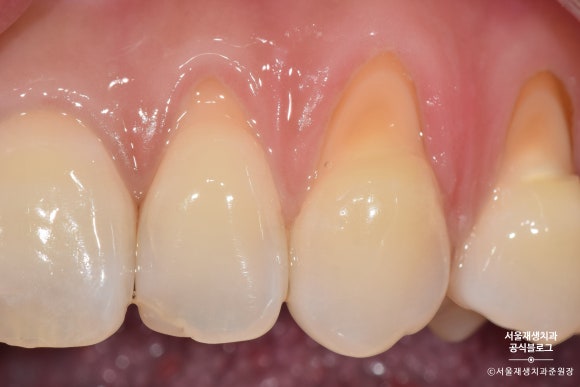

넓고 완만하게 진행된 치경부마모증의 모습입니다.

짠!

완성되었습니다.

치아와 잇몸의 경계부위를 때우기 때문에,

깔끔한 마무리를 위해 잇몸쪽으로 기구 손질을 많이 하게 됩니다.

잇몸 가장자리가 빨개진 것은 대개 하루이틀이면 원래대로 돌아옵니다.

꼼꼼한 치료의 결과라고 생각해주시면 됩니다^^